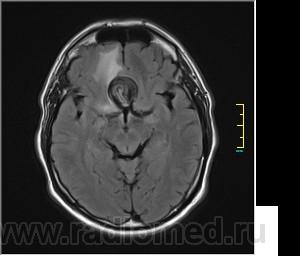

Ax T2 Flair:

частично функционирующая аневризма

Иначе говоря, аневризма с хронической геморрагией, т.к. мы видим фракции крови различного возраста.

По-моему, аневризма с пристеночными тромбами.

Постепенное пристеночное образование тромбов приводит к появлению типичного для аневризмы феномена -слоистости МР сигнала в полости аневризмы. Данная картина демонстрирует слоистый характер тромботических масс в полости аневризмы .Функционрирующая часть имеет низкий сигнал во всех режимах сканирования. Дополнительно-перифокальный отек.

А может более корректно интерпретировать как частично тромбированная аневризма... Уж коь речь идет о фракциях, ну то есть о тромбе по сути.... Ну и плюс перфокальный отек головного мозга (вероятнее цитотоксический+вазогенный).